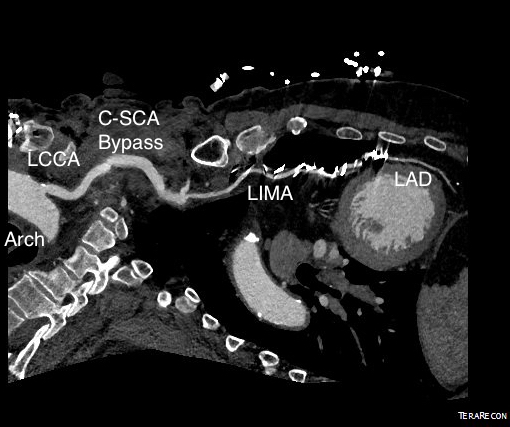

CTA shows the left subclavian artery to be occluded at its origin.

Patient is a 77 year old man with history of HTN, hyperlipidemia, former smoking, and CAD with CABGx5 and bilateral lower extremity bypasses who developed unstable angina consisting of neck and throat pain. He underwent catheterization at an outside hospital and found to have 100% LAD occlusion, a diseased, small patent left main and left circumflex (the profunda femoral artery of the heart!), 100% RCA occlusion, a patent but diseased SVG to distal RCA, and a patent LIMA graft to distal LAD but with severe plaque and near occlusion of his proximal left subclavian artery.

On examination, he had no left brachial pulse, only a monophonic signal there, and bounding femoral pulses where there were the origins of bilateral femoral-tibial bypasses. His radial artery pulse was diminished on the right and absent on the left. Both saphenous veins had been harvested as were arm veins for the left leg bypass.